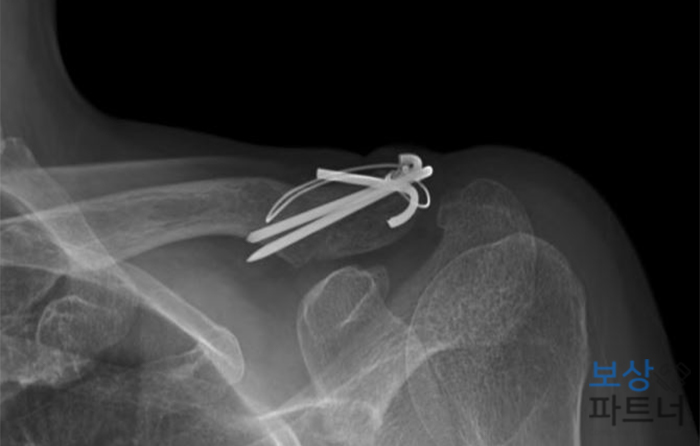

좌측 쇄골 견봉단의 골절 (S42.05)

이 사고로 쇄골이 골절되셨고, 또한 두개골이 골절되어 경막외출혈 증상까지 있으셨는데요. 쇄골 쪽에는 안정적인 골유합을 위하여 금속핀 삽입하여 고정수술 받으시게 되었습니다.